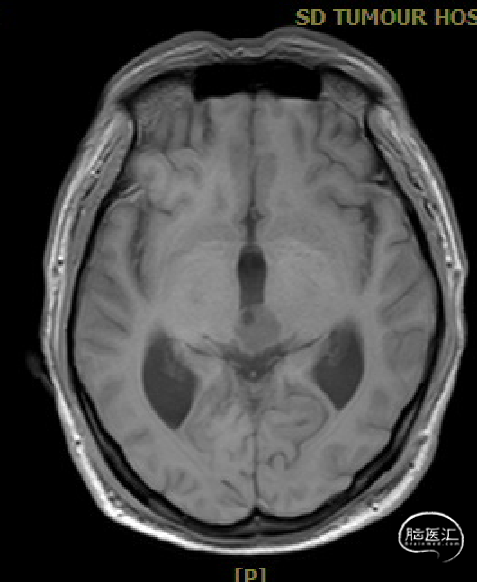

患者5年前无明显诱因出现阵发性头晕,无明显头痛、恶心呕吐等不适,开始未予重视,2022-7-19出现头晕加重,伴视力下降,遂于2022-7-24在当地医院行颅脑MRI提示:松果体区肿瘤伴梗阻性脑积水。

于该院在2022-7-27全麻下行松果体区病灶部分切除活检+神经内镜下第三脑室底造瘘术,术后由于取出肿瘤组织少,未能明确病理结果。患者术后恢复顺利,为进一步治疗就诊于我院。

入院检查

松果体区占位,胶质瘤?生殖细胞肿瘤?

脑积水

脑梗死